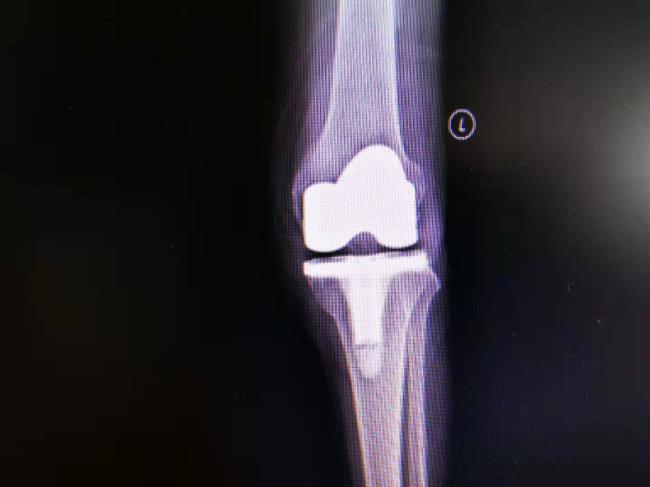

病例2:男65岁,左膝关节退行性变,关节炎,关节疼痛,活动障碍多年。

在我科行全膝关节置换手术,术后疼痛消失,功能恢复。